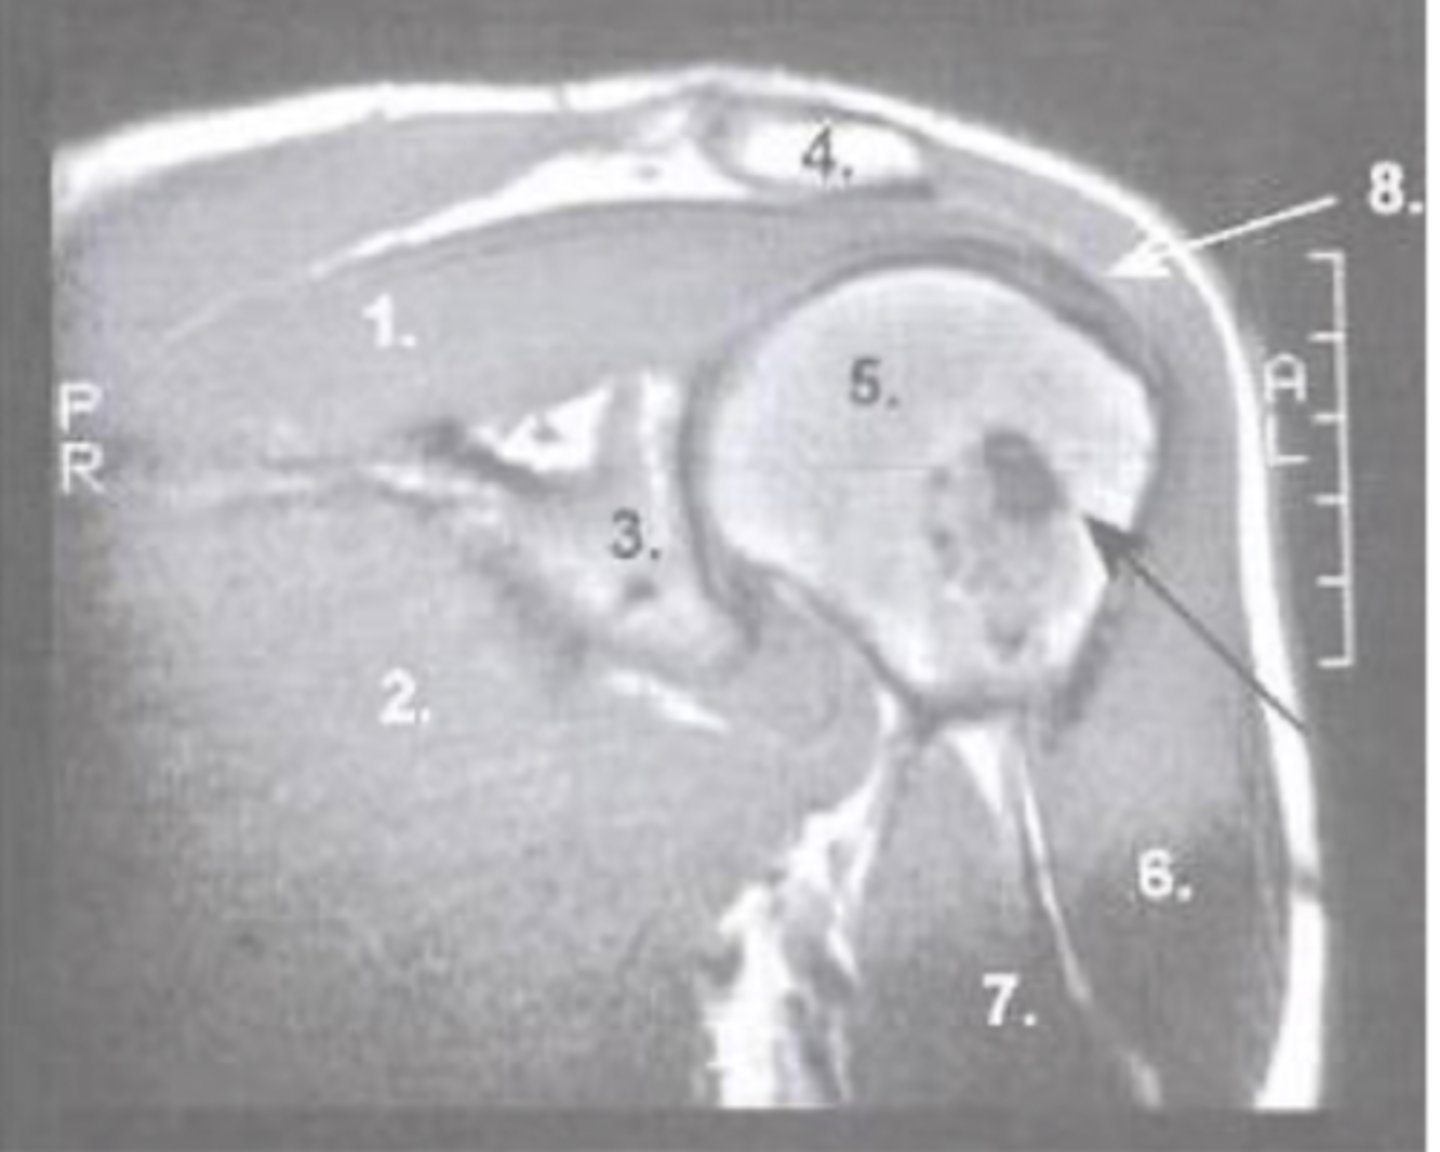

Supraspinatus muscle

What is number 1?

Pec major

What is number 2?

Glenoid

What is number 3?

Acromion

What is number 4?

Humeral Head

What is number 5?

Deltoid

What is number 6?

Biceps Long Head

What is number 7?